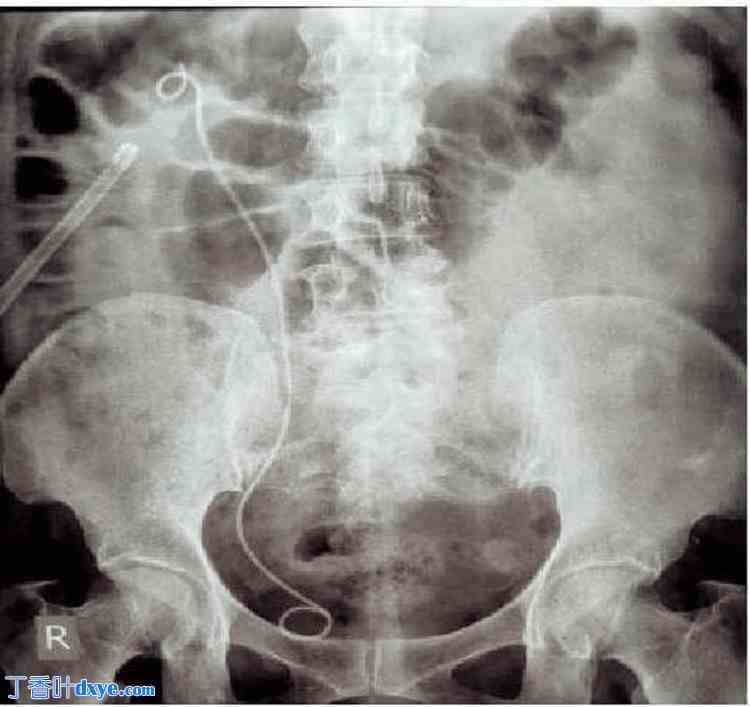

肾脏、输​​尿管和膀胱平片(KUB)显示右侧肾结石(图1)。CT扫描显示左肾在左肾窝内未显影,但已移位至右侧。双肾均存在旋转不良。左侧输尿管跨越中线。双侧膀胱输尿管连接处位置正常。

图1. 肾脏、输尿管和膀胱平片。

箭头指示右侧肾结石。